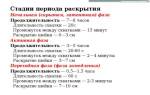

В течение 39 недели беременности могут участиться схватки, причем на этом этапе схватки могут быть двух типов: «ложные» и «родовые».

Ложные схватки могут начаться за несколько недель , или даже месяцев до ожидаемого срока родов. Такие схватки помогают ребенку принять правильное положение в утробе матери, а также подготовить матку к родам.

Такие схватки нерегулярны, непродолжительны, ощущаются преимущественно в нижней и передней частях живота.

Родовые же схватки регулярны, ритмичны, не ослабевают, учащаются с нарастающей силой. Обычно они имеют место после отхождения околоплодных вод. При этом раскрытие шейки матки происходит на 4 см. Начавшимися роды формально считаются только после появления сильных и частых схваток.

Боль при схватках приступообразная, четко ощущается её возникновение, усиление, достижение пика и постепенное уменьшение, потом наступает период без болевых ощущений. Сначала схватки перед родами идут с промежутком 15-30 минут и длятся 10-15 секунд.

Первые несколько часов они приносят скорее небольшой дискомфорт, чем боль. Постепенно продолжительность и сила схваток увеличиваются, а интервалы уменьшаются.

Как происходят схватки? Схватки перед родами развиваются постепенно, поэтому можно выделить три стадии:

- Первая стадия — начальная, длится 7-8 часов. В это время схватки происходят с интервалом примерно в 5 минут, а продолжительность их — 30-45 секунд.

- Вторая фаза — активная. Ее продолжительность около 5 часов, сокращения матки становятся чаще и длятся дольше — с интервалом 2-4 минуты, продолжительность схваток достигает 60 секунд.

- Последняя, переходная, фаза — длиной от получаса до 1,5 часов. Схватки становятся еще чаще и дольше. Они могут происходить с промежутком в минуту и иметь продолжительность от 70 до 90 секунд.

Если роды не первые, процесс проходит быстрее, поэтому не стоит затягивать с поездкой в роддом!